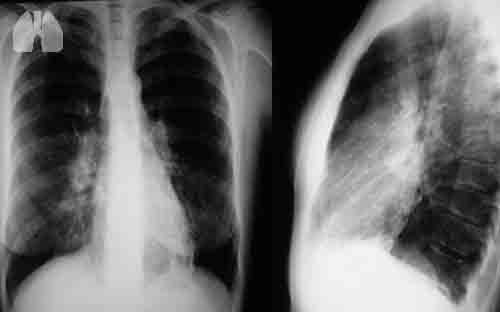

Primary ciliary dyskinesia (PCD) has been considered to be relatively mild disease, especially compared to cystic fibrosis (CF), but studies on lung function in PCD patients have been few and small.

This study compared lung function from spirometry of PCD patients to normal reference values and to published data from CF. We calculated z-scores and percentage of predicted values for FEV1 and FVC using the Global Lung Function Initiative 2012 for 991 patients from the international PCD (iPCD) Cohort. We then assessed associations with age, sex, country, diagnostic certainty, organ laterality, body mass index and age at diagnosis in linear regression models. Lung function in PCD patients was reduced compared to reference values in both sexes and all age groups. Children aged 6–9 years had the smallest impairment (FEV1 z-score −0.84 [−1.03 to −0.65], FVC z-score −0.31 [−0.51 to −0.11]). Compared to CF patients, FEV1 was similarly reduced in children (age 6–9 years PCD, 91% [88–93%]; CF, 90% [88–91%]), but less impaired in young adults (age 18–21 years PCD, 79% [76–82%]; CF, 66% [65–68%]). The results suggest that PCD affects lung function from early in life, which emphasizes the importance of early, standardised care for all patients.